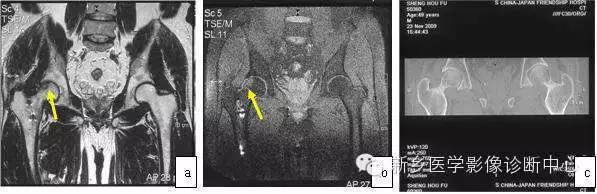

典型ONFH的MRI表现为T1WI低信号带包绕脂肪信号,T2WI出现双线征(double line sign),T2WI抑脂像或STIR序列出现片状或带状高信号(图1),此异常信号改变多数位于闭合的骨骺线以近,但部分ONFH的坏死信号带可穿透骨骺线至股骨头远端,少数可穿透股骨颈部。约20%的ONFH不出现T2WI的双线征。如在股骨头颈及转子部出现骨髓水肿,提示坏死病灶进展到围塌陷期。

图1 典型的股骨头坏死MRI图像(a)T1WI带状低信号;(b)T2WI双线征;(c)T2WI抑脂像示带状高信号

2 诊断早期ONFH最可靠的MRI图像

具体表现为T1WI蜿蜒曲折的低信号带。北京市SARS骨坏死专家诊疗组依据上述图像诊断的176例ONFH以及否定ONFH诊断的363例的应用皮质激素的SARS患者,经7年随访,至今仍未发现一例过度诊断,也未发现一例漏诊,证明此图像对ONFH诊断的特殊价值。MRI显示股骨头信号非同质改变,只要无带状低信号,就不应诊断为股骨头坏死。